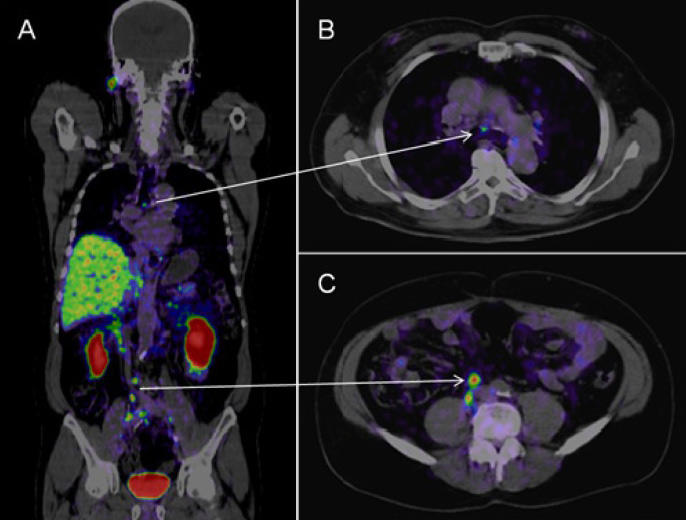

Los exámenes de medicina nuclear brindan información de alta precisión que, por lo general, no se puede obtener con otros procedimientos de imágenes y presentan una mejor relación costo beneficio, permitiendo evitar las cirugías exploratorias. Mediante la identificación de cambios a nivel celular, las imágenes por PET pueden detectar la aparición temprana de la enfermedad antes de que sea evidente con otros estudios por imágenes.

Imagen referencial de examen Pet CT